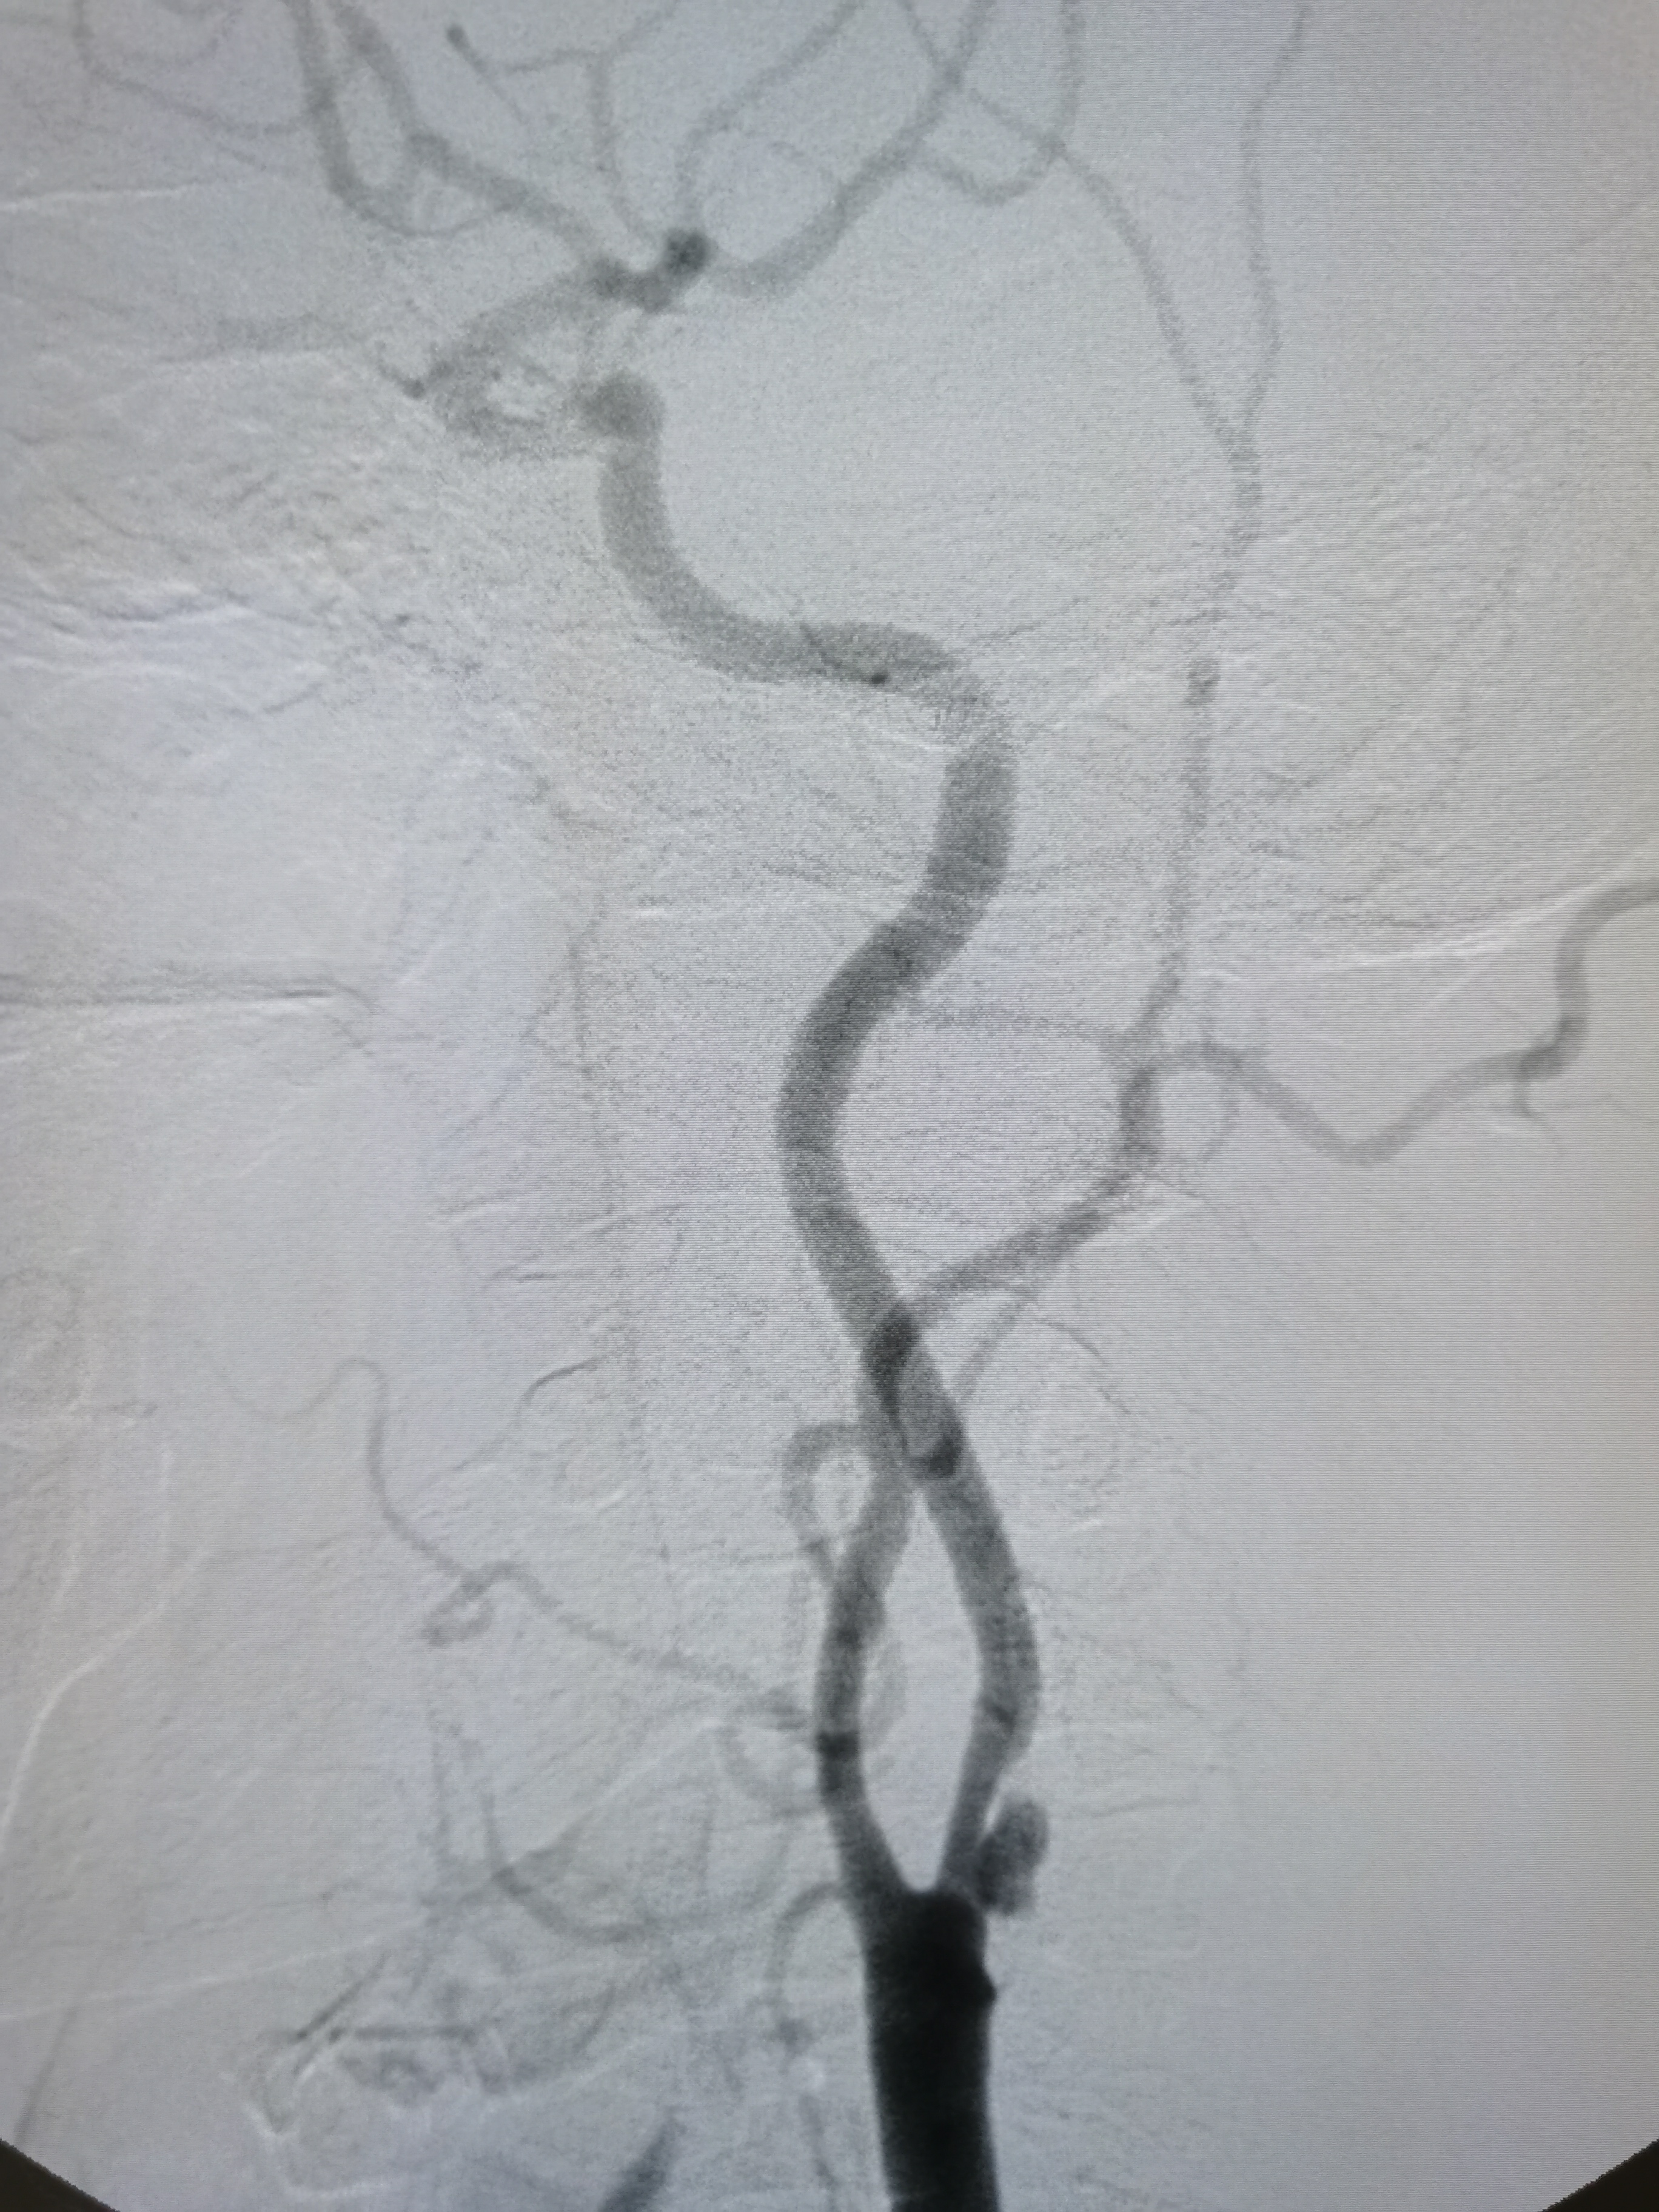

左侧颈内动脉狭窄伴溃疡形成。

颅内段显影可。

双侧大脑前动脉共干。